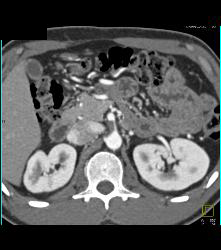

Plaque in Proximal SMA